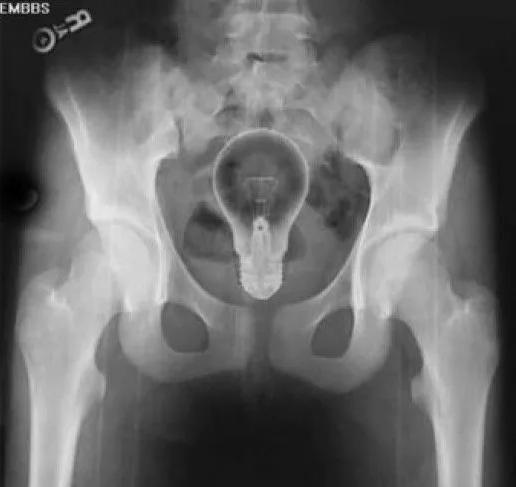

Врач предупредил об опасности введения бытовых предметов в прямую кишку Аноним 28/01/26 Срд 09:03:39 19129725

Колопроктолог Даниэль Броско призвал не вводить бытовые предметы в прямую кишку, поскольку такая сексуальная практика опасна для здоровья. Его слова передает издание Terra.

Броско предупредил, что из-за инородных тел в анусе может возникнуть перфорация кишечника.

В таком случае хирургическое вмешательство неизбежно, подчеркнул он.

В худшем случае все может закончиться смертью, как это случилось с одним из пациентов доктора, а в лучшем — установкой колостомического мешка

. «Поскольку вам придется перенести операцию, вам потребуется колостомия, другого выхода нет, и восстановить кишечник после этого очень сложно. Поэтому это крайне серьезное, очень тяжелое дело», — отметил врач.

Если бытовой предмет все-таки застрял в прямой кишке, врач призвал не принимать слабительные средства. Вместо этого следует сразу же обратиться в больницу. Тем же, кто хочет исследовать свое тело, посоветовал использовать исключительно секс-игрушки.